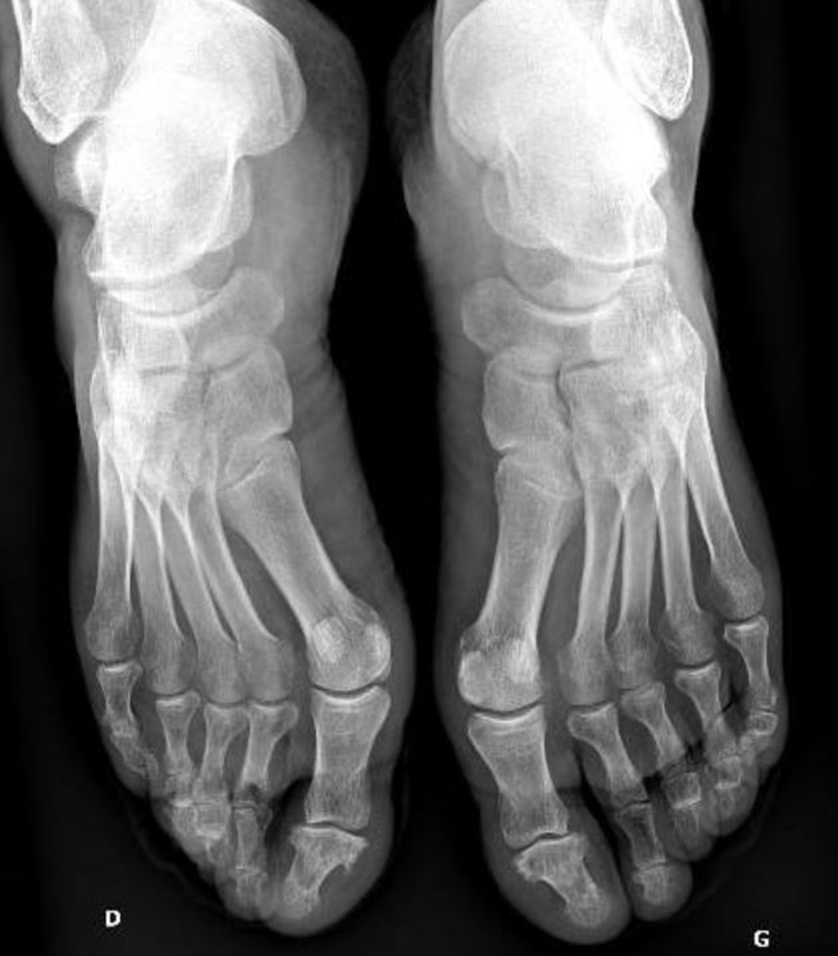

M. G. est suivi pour une hypertension artérielle, une dyslipidémie et un antécédent d’ulcère gastrique. Il a été opéré d’une hernie inguinale droite il y a cinq ans, et a subi une appendicectomie et une amygdalectomie dans l’enfance. Il n’y a pas d’antécédent familial notable. Son traitement est le suivant : amlodipine 10 mg/j, ramipril 5 mg/j, atorvastatine 40 mg/j, lansoprazole 30 mg/j. Il ne fume pas et boit 2 verres de vin par jour. Il ne décrit pas de signe associé notamment pas d’altération de l’état général, pas de fièvre, pas de rachialgie, pas de trouble digestif, pas d’antécédent ophtalmologique. Vous complétez votre examen clinique. Les paramètres vitaux sont les suivants : pression artérielle (PA) = 141/86 mmHg ; fréquence cardiaque (FC) = 76/min ; température (T°) = 36,7 °C ; saturation en oxygène (SpO2) = 99 %. L’auscultation cardiopulmonaire et la palpation abdominale sont sans particularité. L’examen cutané retrouve l’aspect suivant : Figure 1 (Source : Salomé Abdellaoui, La Revue du Praticien)

Le patient a une hyperkératose plantaire, ce qui peut s’intégrer dans le cadre d’un psoriasis, avec souvent une atteinte similaire des mains. Le diagnostic d’arthrite septique est peu probable : pas de fièvre, notion d’antécédent similaire résolutif après la prise d’anti-inflammatoires, association à un psoriasis qui rend le diagnostic de spondylarthropathie plus probable.

Vous retrouvez la même atteinte au niveau des mains. La face dorsale des pieds a l’aspect suivant : Figure 2 (Source : Salomé Abdellaoui, La Revue du Praticien)